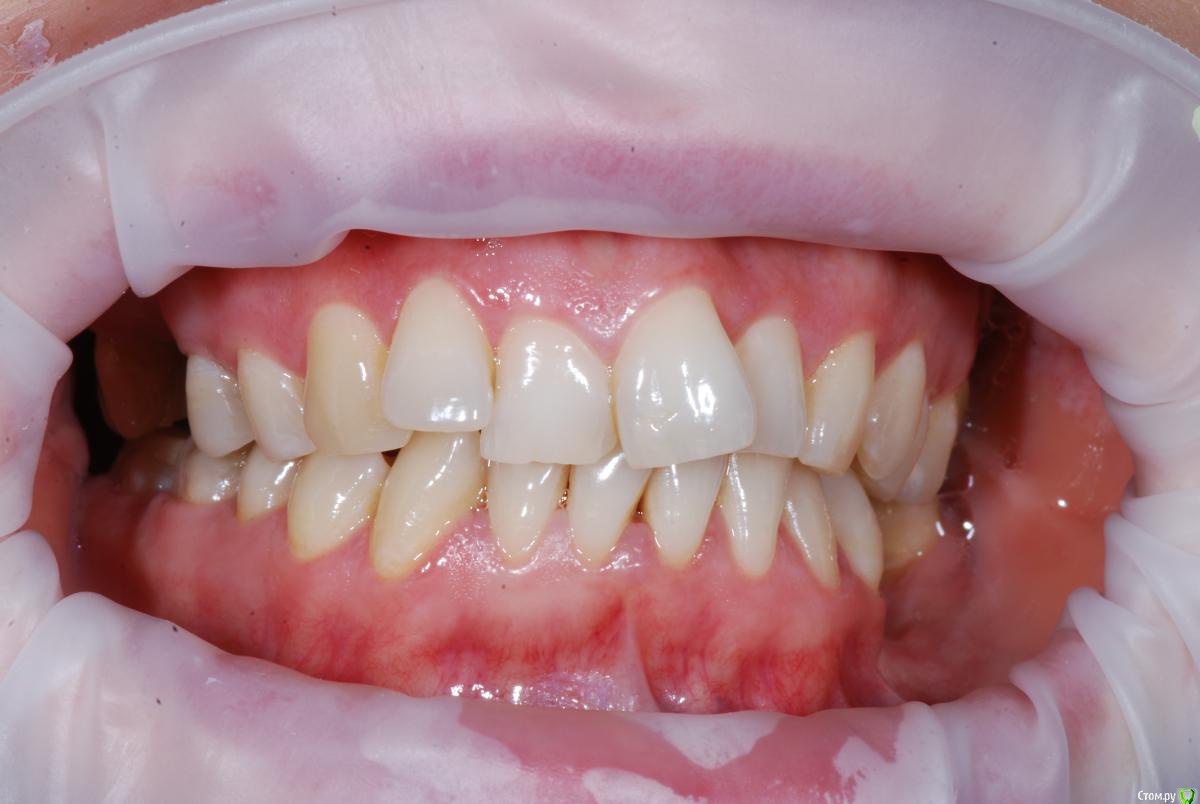

Afffinity Опубликовано 13 декабря, 2016 Автор Поделиться Опубликовано 13 декабря, 2016 Вот именно в чем в принципе сомневаетесь? и на моделях надо указывать анатомический центр, тогда сразу понятнее станет чего и куда и на сколько. ну Вы хотя бы свои мысли озвучили бы, расчет трг, характер асимметрии (в каком положении головки, что на КТ?) ... полностью Вам не распишут план, вопросы более конкретные попробуйте задать для коллегЕсли кратко то по расчетам ТРГ 2й скелетный класс, в цифрах завтра распишу. Прошу прощения что сразу не выложил. 2е, смущает смещение центральной линииПланируем установить систему Damon Q. Самый главный вопрос, возмножо ли в данном случае обойтись без удаления премоляров? Ссылка на комментарий